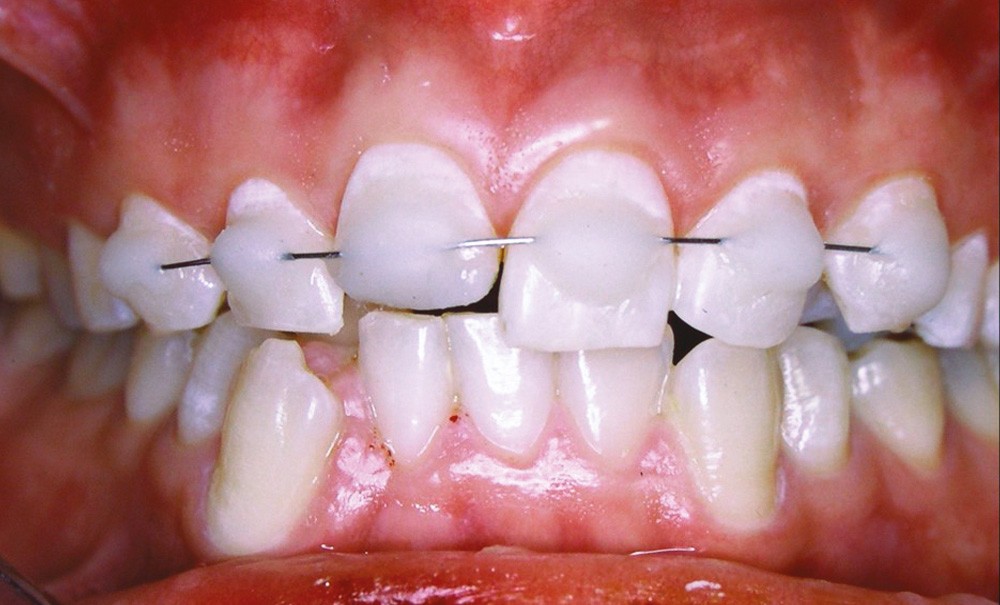

Le terme « luxation » est un terme générique qui englobe plusieurs traumatismes distincts. Les dents le plus souvent affectées sont les incisives maxillaires et mandibulaires. La terminologie diagnostique utilisée pour identifier avec précision ces traumatismes figure dans le tableau ci-dessous (tableau 1). Les luxations avec déplacement et/ou mobilité requièrent la pose d’une contention, contrairement à celles sans déplacement dentaire.

Ainsi, les dents ayant souffert d’une concussion ou d’une subluxation ne requièrent pas la pose d’une contention. Après repositionnement, une contention sera néanmoins nécessaire dans les cas d’extrusion, luxation latérale, intrusion, expulsion et fracture radiculaire avec luxation du fragment coronaire.